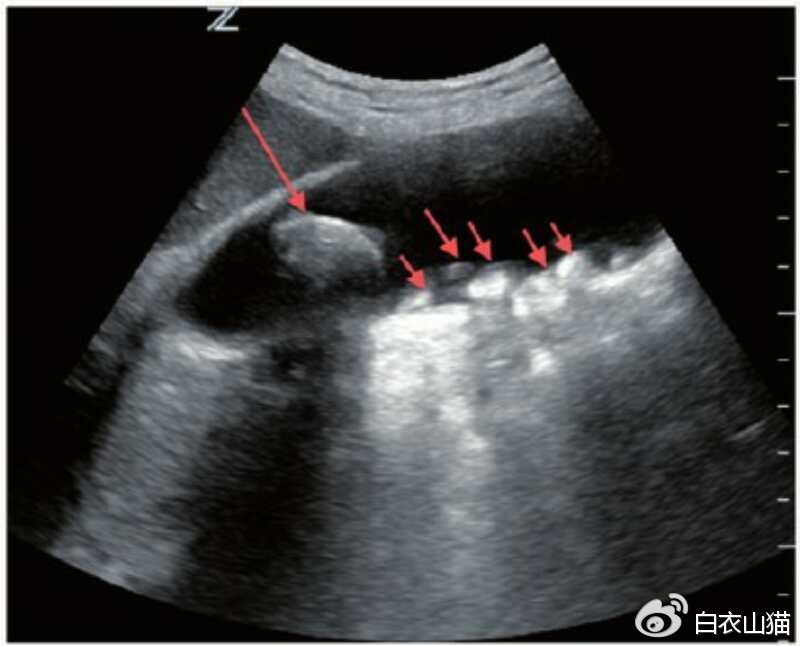

B超怎么来判断息肉和结石呢?

结石的B超表现有:胆囊腔强回声、后 方伴会有声影、声像具体表现会随着患者体位的改变 而发生移动现象。

红箭头指向结石。

息肉的B超表现有: 胆囊壁有强或稍强回声光团,其后无声影, 声像具体表现不会随着患者体位的改变 而发生移动现象。

部分结石,比如胆固醇结石,比较疏松的时候,可以没有声影。这个时候,恰好结石又粘附在胆囊壁上,当然不会随体位变化而移动啦。这部分结石,会被B超下判断为息肉。